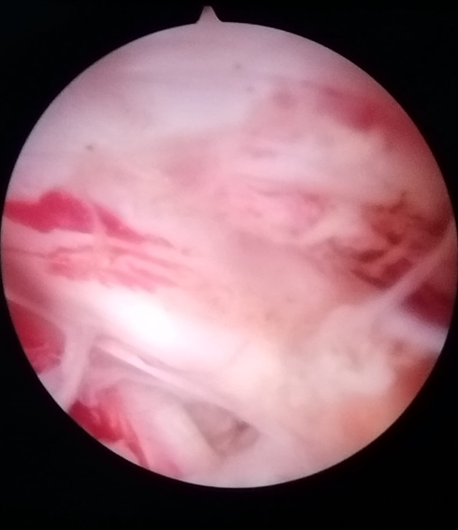

В отличие от традиционной хирургии позвоночника, которая требует больших разрезов и значительного рассечения мышц, при эндоскопической хирургии используется небольшая трубка, называемая эндоскопом. Эндоскоп, оснащённый крошечной видеокамерой и специализированными хирургическими инструментами, вводится через небольшой разрез, обычно около 6-8 мм. Это позволяет хирургу получить чёткое увеличенное изображение позвоночника и точно воздействовать на поражённую область, будь то выпячивание межпозвоночного диска, костная шпора или другие проблемы с позвоночником, не затрагивая окружающие мышцы и ткани.

Проведение операции: через трубку хирург вводит эндоскоп — небольшую камеру, которая обеспечивает чёткое изображение внутри позвоночника. С помощью специальных инструментов хирург удаляет проблемные ткани, такие как грыжи межпозвоночных дисков или костные наросты, которые могут давить на нервы и вызывать боль. В отличие от некоторых клиник, которые рекламируют «лазерную операцию на позвоночнике», мы используем комбинацию инструментов, в том числе лазер и ультразвуковую энергию, чтобы точно воздействовать на проблемную область.